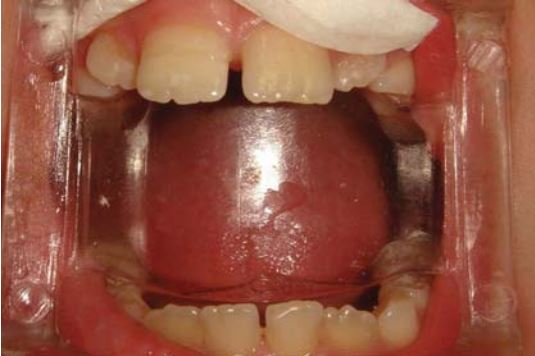

Gắn lại mảnh gãy răng cửa hàm dưới thường khó vì kích thước rất nhỏ (H18.14).

Có thể sử dụng dụng cụ giữ có đầu dính (Pic-n-Stic Pulpdent Corp) (H18.15).